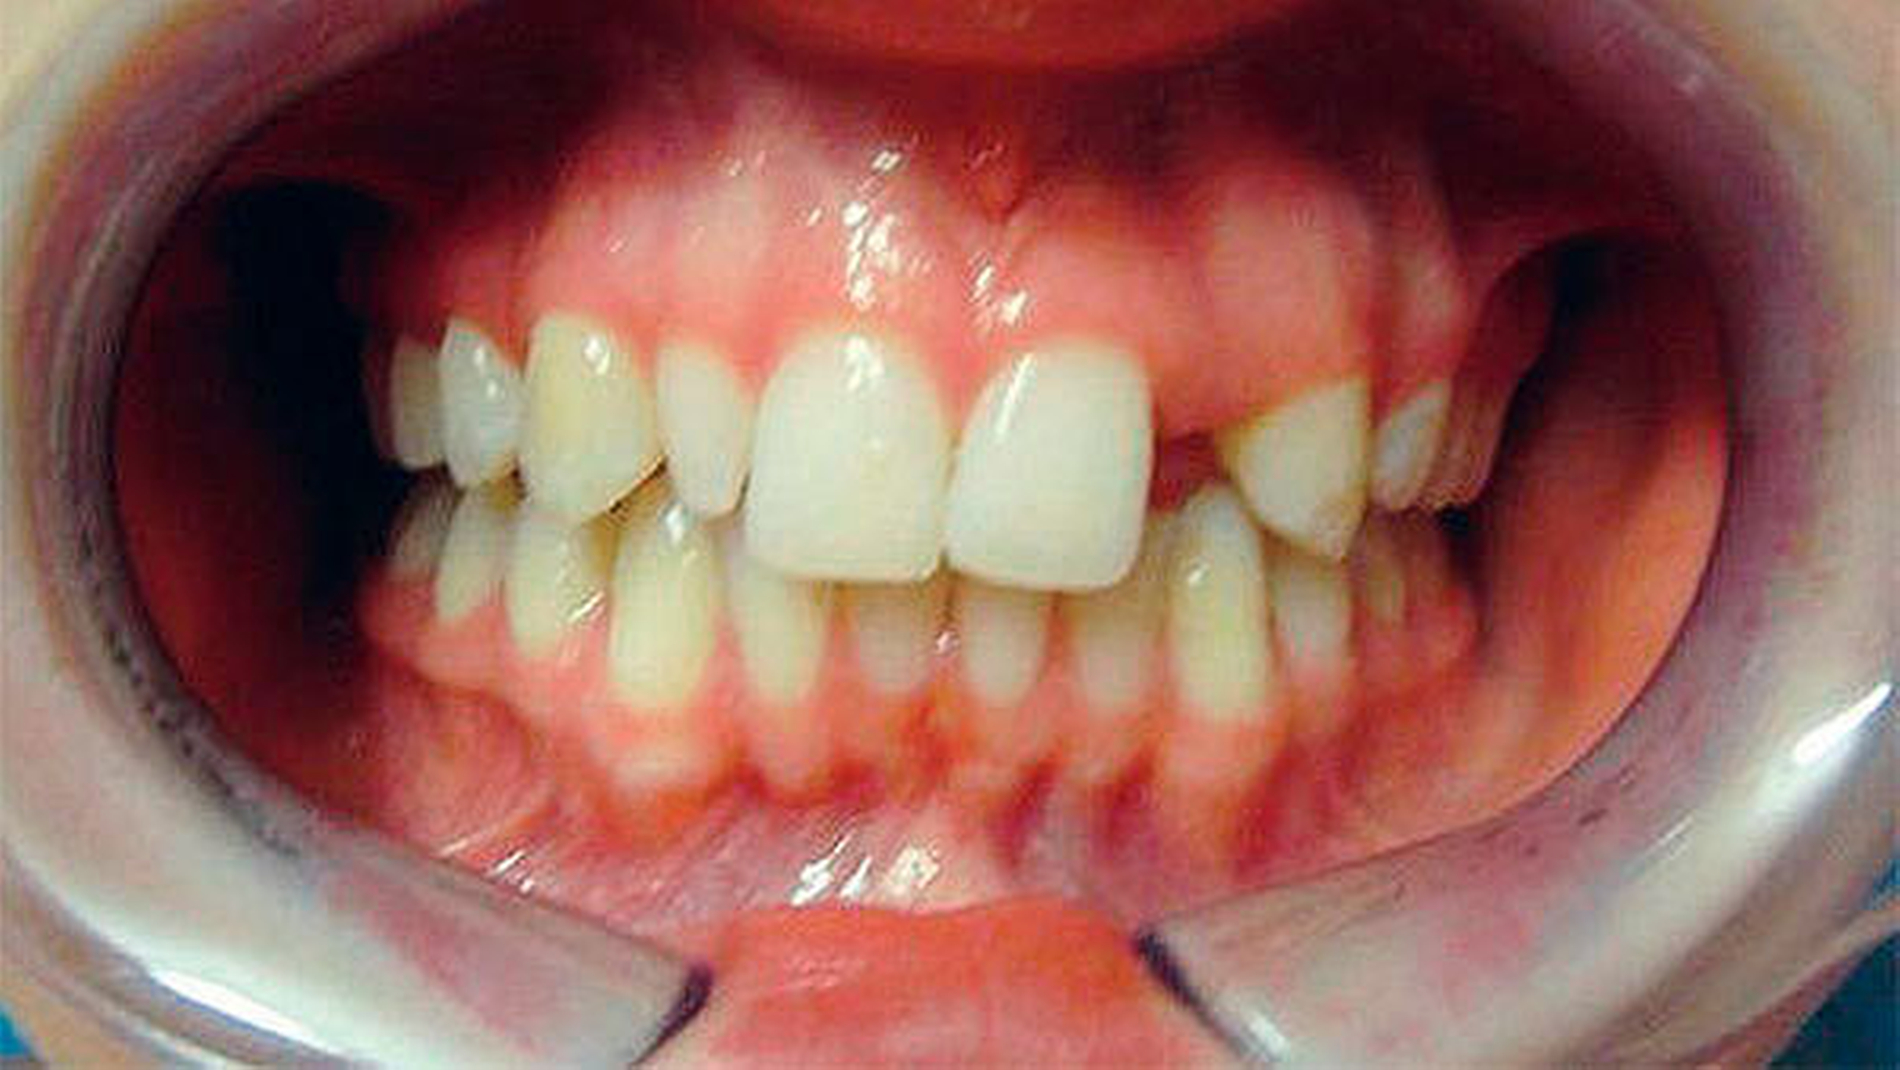

Eine 20-jährige Patientin stellte sich zur Implantat- und Distraktionsberatung in der Abteilung für Mund-, Kiefer- und Gesichtschirurgie vor. Diagnostisch lagen eine mandibuläre Retrognathie, retinierte und verlagerte Zähne 18, 28, 38 und 48, ein Zapfenzahn 12, ein fehlender Zahn in regio 022, eine Mittellinienverschiebung und ein Engstand der Oberkieferfront vor (Abbildung 1). Im Rahmen der klinischen Untersuchung und basierend auf dem Auswertungsergebnis der DVT wurde bei der Patientin im Hinblick auf mögliche therapeutische Maßnahmen eine differenzial-therapeutische Beratung durchgeführt.

Klinisch und radiologisch lag eine konvergierende Wurzelstellung der Zähne 21 und 23 vor. Eine unkomplizierte implantatprothetische Versorgung der Lücke 022, das heißt ohne Verletzung der benachbarten angulierten Zähne, erschien nicht möglich. Die Schwierigkeit bestand darin, die Lücke 022 zu öffnen, was sich bislang aufgrund einer festsitzenden Apparatur als frustran erwiesen hatte. Der Patientin wurde aufgrund der vorliegenden Diagnose eine parodontal akzelerierte osteogene Orthodontie (PAOO) im Bereich des linken Oberkiefers empfohlen.

Darüber hinaus wünschte sich die Patientin, auch die Lücke mit dem Zapfenzahn 12 zu öffnen, damit weitere, ästhetische Korrekturen durchgeführt werden konnten. Auf den Zapfenzahn 12 sollte eine größere Krone gesetzt werden, gegebenenfalls sollten eine Extraktion und eine Implantation erfolgen. Wir stellten der Patientin frei, auch dort das PAOO-Verfahren einzusetzen. Die Durchführung beider Korrekturen erschien in Vollnarkose mit gleichzeitiger Entfernung der Weisheitszähne indiziert.